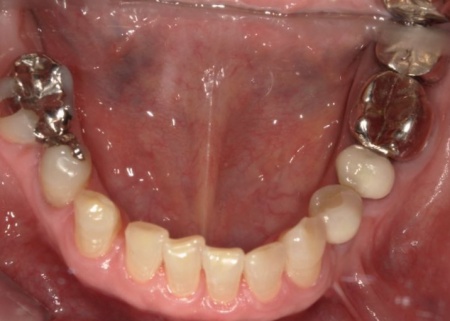

70代女性 歯根が割れた左下奥歯を抜きインプラントで噛み合わせを回復させた症例

レントゲン撮影を行って詳しく拝見したところ、左下奥歯(第1小臼歯)の歯根が割れていました。

まず、周辺組織に負担をかけないよう配慮しながら、慎重に左下奥歯(第1小臼歯)を抜きます。

抜歯後は骨や歯茎の回復を待ち、口腔内の状態が安定したことを確認して、インプラント埋入手術へ進みました。

後日、インプラントと骨がしっかりと結合したら、精密な型取りを行い、被せ物を作製します。

最後に完成した被せ物を装着し、痛みや違和感がないか、見た目や噛み合わせに問題がないかを確認して、治療を終了しました。